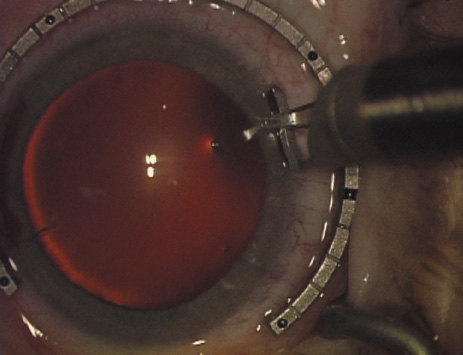

ways. Our preferred method makes use of a modified Fine-Thornton fixation

ring (Nichamin Fixation Ring and Gauge; Mastel Precision, Storz, Rhein

Medical). This instrument serves to fixate and position

the globe in order to optimize incision placement, as well as to delineate

the extent of arc to be incised. One visually extrapolates from

the limbus to marks on the surface of the ring. Each incremental mark

is 10 degrees apart, and bold hash marks (180 degrees) opposite

to each other serve to align and center the incision over the steep

meridian. This approach obviates the need to ink and physically mark

the cornea. If one desires, particularly when first gaining experience

with LRIs, a two-cut RK marker may be used to place ink marks upon the

cornea to show the exact extent of arc that is to be incised, in conjunction

with the fixation ring/gauge (Fig. 4). Alternatively, various press-on markers are available, such as

markers, rings, and blades for performing LRIs.  Fig. 4. The Nichamin Fixation Ring and Gauge serves to both fixate the globe and

delineate the extent of arc to be incised; a two-cut radial marker may

be used to mark the extent of arc to be incised, and the Mastel Nichamin

Force AK Diamond Blade with preset depth of 600 microns. Fig. 4. The Nichamin Fixation Ring and Gauge serves to both fixate the globe and

delineate the extent of arc to be incised; a two-cut radial marker may

be used to mark the extent of arc to be incised, and the Mastel Nichamin

Force AK Diamond Blade with preset depth of 600 microns.